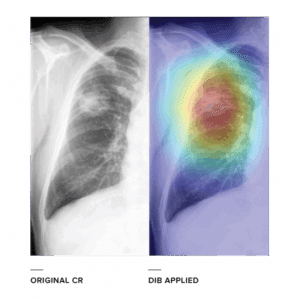

In contrast to conventional Computer-Aided Detection (CAD) that is heavily dependent on guidance (lesion annotation) of radiologists, DIB lets the machine define important diagnostic features by itself solely from large-scale data. This can be possible by employing feature-learning capability of deep convolutional neural network.

DIB for chest radiography serves to act as a “second reader” in detection and differentiation of abnormal lesions in chest x-rays, including pneumonia, emphysema, diffuse interstitial lung disease, tuberculosis, lung cancer, and pulmonary metastasis, with high diagnostic performance. DIB is expected to help both general practitioners and radiologists interpret CRs more efficiently and accurately.